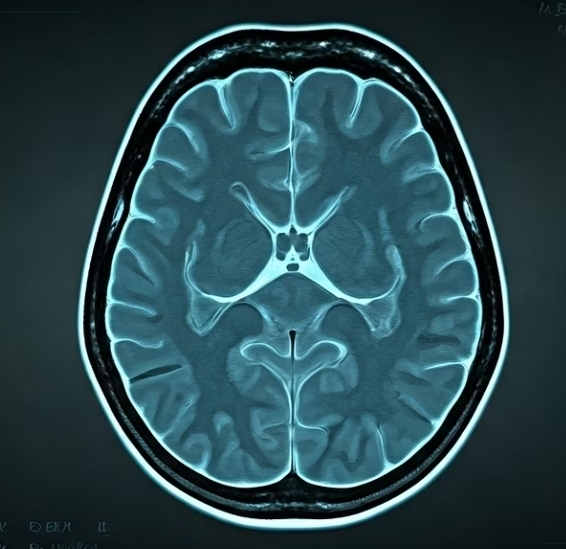

니파바이러스의 가장 심각한 점은 감염이 신경계로 빠르게 전파될 수 있다는 것입니다. 초기 증상이 나타난 이후, 일부 환자들은 수일 내에 의식 혼미, 발작, 방향 감각 상실 등의 신경학적 이상 증상을 보일 수 있습니다.

이러한 니파바이러스 증상은 뇌염의 전조증상일 수 있으며, 실제로 많은 니파바이러스 감염자들이 바이러스성 뇌염으로 발전해 혼수상태에 빠지거나 사망에 이르는 경우도 있습니다. 따라서 발열과 두통에 더해 정신 혼란이나 반응 저하가 나타난다면 반드시 즉각적인 의료기관 방문이 필요합니다.